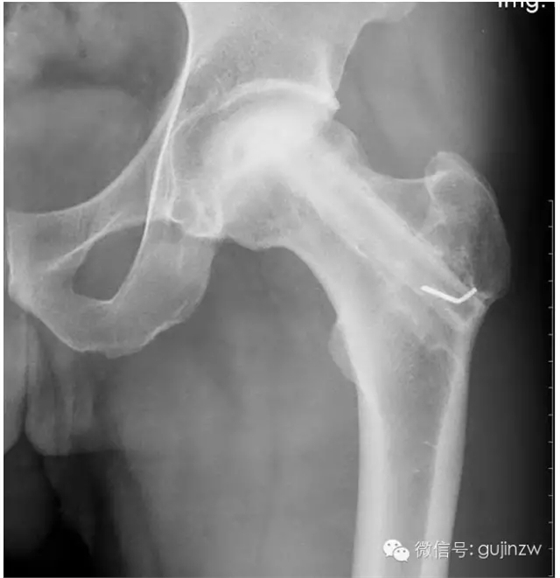

a、適應(yīng)癥:骨缺血性壞死、一般植骨術(shù)難以奏效時。

b、要點:吻合血管,保存血運